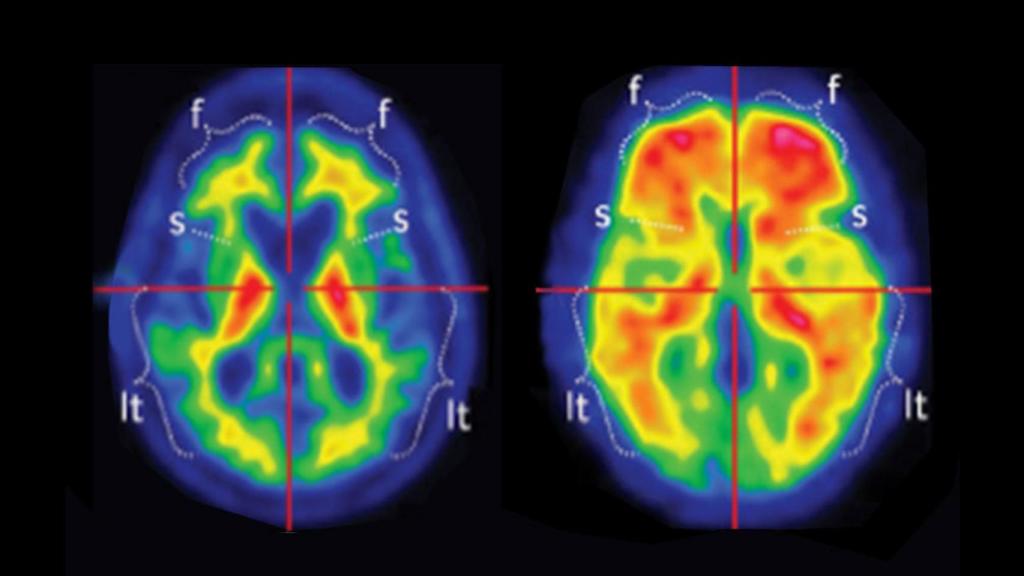

Imagen de un PET cerebral. A la izquierda, las placas de beta-amiloide en un paciente sano y a la derecha en un paciente con alzheimer.

Imagen de un PET cerebral. A la izquierda, las placas de beta-amiloide en un paciente sano y a la derecha en un paciente con alzheimer. Quirónsalud.